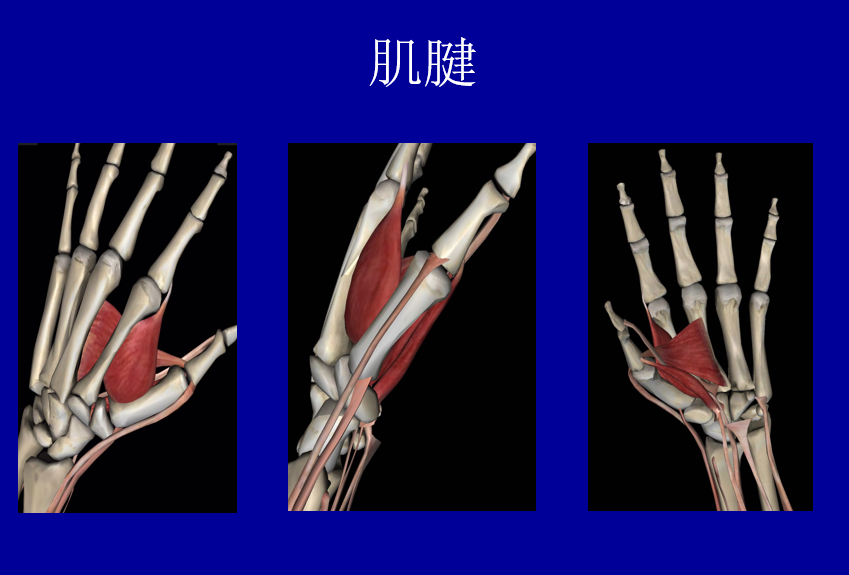

解剖

第一腕掌关节位于拇指运动轴的基底,在拇外展和对掌中起着关键作用,关节为鞍状。关节囊松驰,周围有多条韧带加强,关节屈曲30-50度,伸0-5度,内收0-5度,外展35-40度。